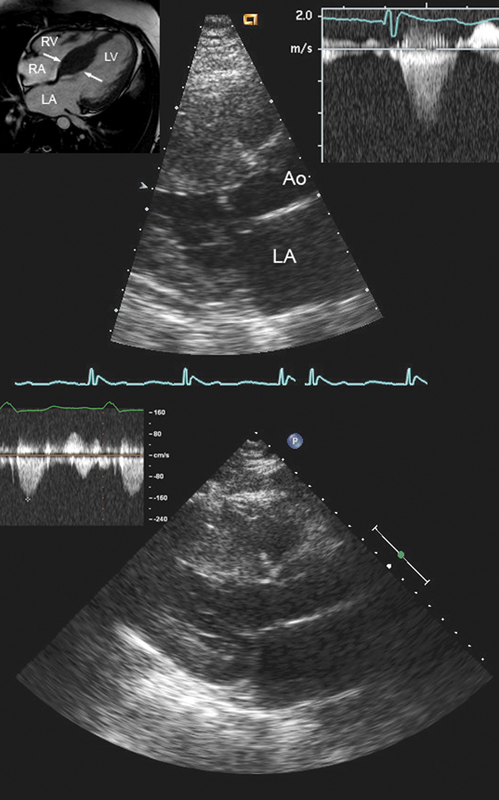

فحوصات تشخيصية لبعض امراض القلب والشرايين التاجية